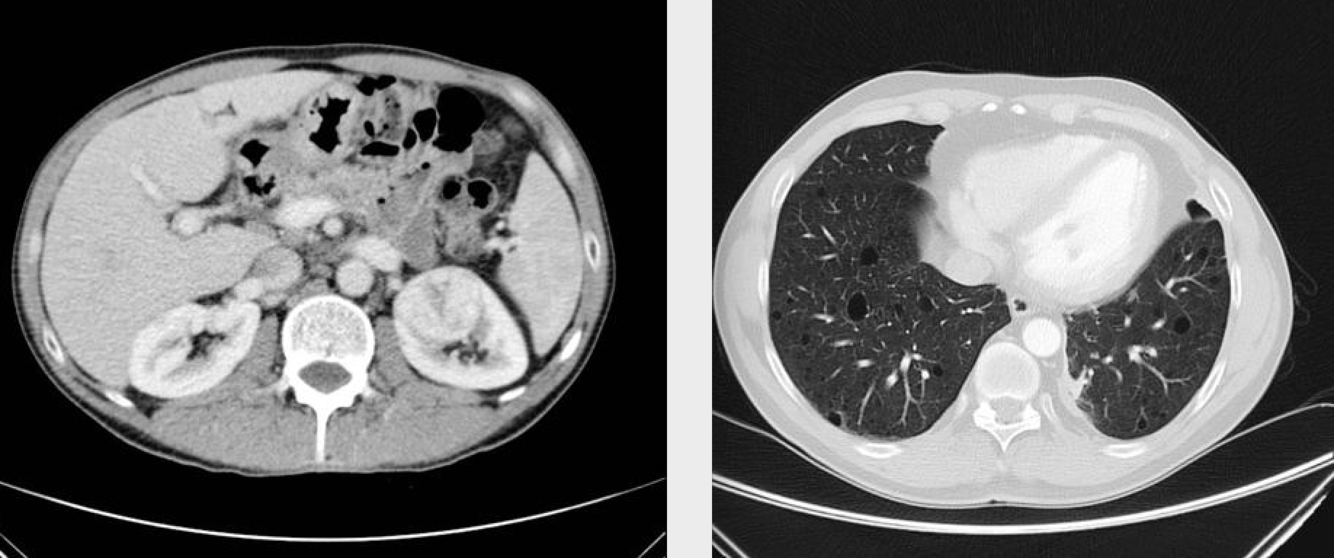

Birt-Hogg-Dubé syndrome

Dr Patrick Rock◉ and Dr Maxime St-Amant◉ et al.

Birt-Hogg-Dubé syndrome or folliculin gene-associated syndrome is a genetic multisystemic disease mainly characterised by:

multiple lung cysts and secondary spontaneous pneumothoraces

multiple bilateral renal tumours (particularly chromophobe renal cell cancer and oncocytoma)

cutaneous manifestations (angiofibromas, perifollicular fibromas, acrochordons, fibrofolliculomas, etc.)

Birt-Hogg-Dubé syndrome carries an estimated 25% risk of renal cell carcinoma 12.

Radiographic features

CT

Lung cysts in Birt-Hogg-Dubé syndrome are usually multiple and have a lower zone predominance 11. Cyst morphology tends to be variable within each patient, with cysts commonly oval or lentiform and septated when large 4. The presence of paramediastinal cysts when disproportionate in number or oval (floppy) in shape is another distinguishing characteristic 11.